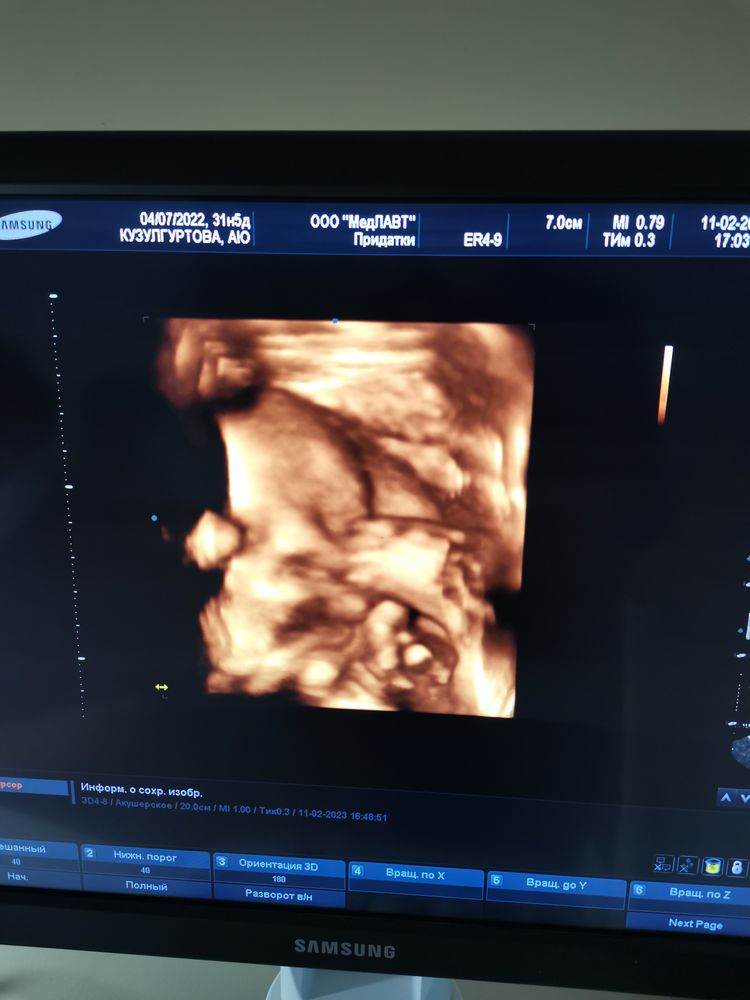

Наши 32 нед. и шейка... 😬

Я думала, на таком сроке 24 мм норма…

Лида, норма от 28, увы, я не дотянула🤷‍♀️